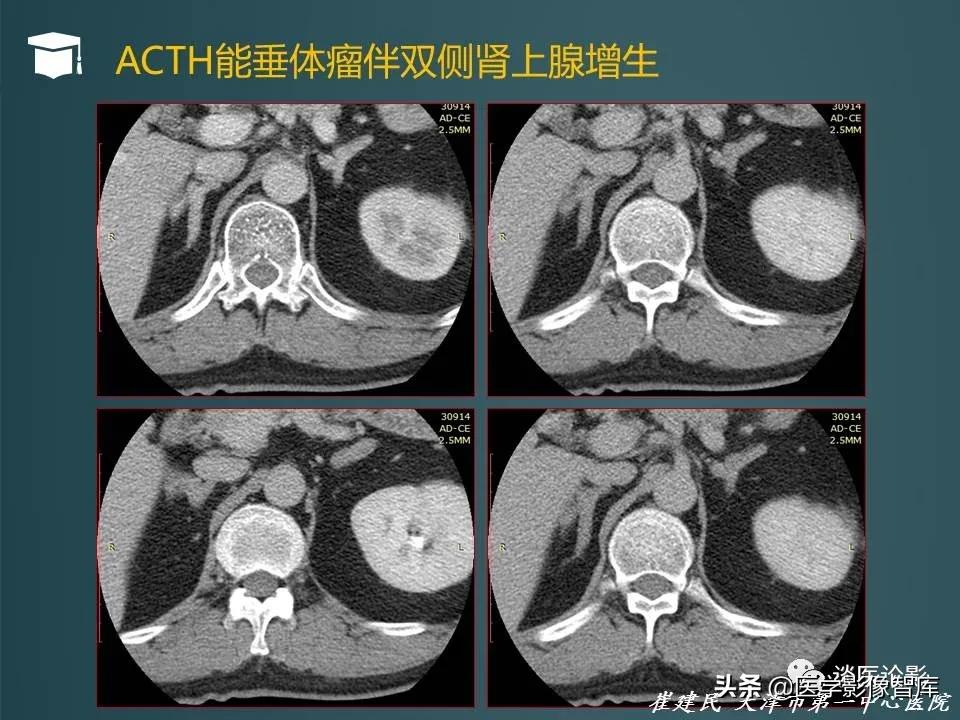

- 库欣病:由垂体促肾上腺皮质激素瘤所致,占内源性库欣综合征的80%-85%

- 真性库欣病可以通过地塞米松抑制试验验证,小剂量地米抑制试验不被抑制,大剂量地米抑制试验被抑制即可证明为垂体性ACTH增高